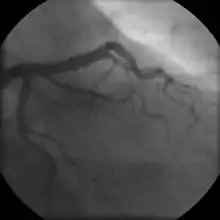

- Coronary angiography

Stable angina is the most common form of ischemic heart disease, and is associated with reduced quality of life and increased mortality. It is caused by epicardial coronary stenosis which results in reduced blood flow and oxygen supply to the myocardium.[72] Stable angina is characterized as short-term chest pain during physical exertion caused by an imbalance between myocardial oxygen supply and metabolic oxygen demand. Various forms of cardiac stress tests may be used to induce both symptoms and detect changes by way of electrocardiography (using an ECG), echocardiography (using ultrasound of the heart) or scintigraphy (using uptake of radionuclide by the heart muscle). If part of the heart seems to receive an insufficient blood supply, coronary angiography may be used to identify stenosis of the coronary arteries and suitability for angioplasty or bypass surgery.[73]